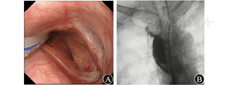

例3 患者男,26岁,2011年因脑外伤行气管切开,保留气管套管3个月余,拔管后患者呛咳明显,行胃镜检查示距门齿17~19 cm处可见高位食管气管瘘。考虑瘘口位置较高,手术创伤和风险较大,患者拒绝行外科手术治疗。2016年患者先后2次行OTSC(over-the-scope clip)吻合夹夹闭瘘口,因无操作空间,手术效果欠佳。入院时瘘口长径仍为1 cm。患者于2017年11月13日就诊于江苏省人民医院,于11月15日行经口胃镜下OverStitch缝合术,但由于高位食管气管瘘,经口胃镜下操作空间有限,手术失败。外科会诊后,于2017年11月20日行腹腔镜和胃镜联合下腹腔镜经皮胃造口,胃镜经皮、胃、食管逆行缝合高位食管气管瘘(图6)。手术过程顺利,术中使用1根缝合线,缝合6针。术中和术后无不良事件出现。总手术时间约为150 min。术后1周行上消化道造影检查,气管内未见造影剂(图7A),于11月28日出院。术后半年随访,患者自诉症状已明显缓解,复查胃镜示瘘口已闭合(图7B)。